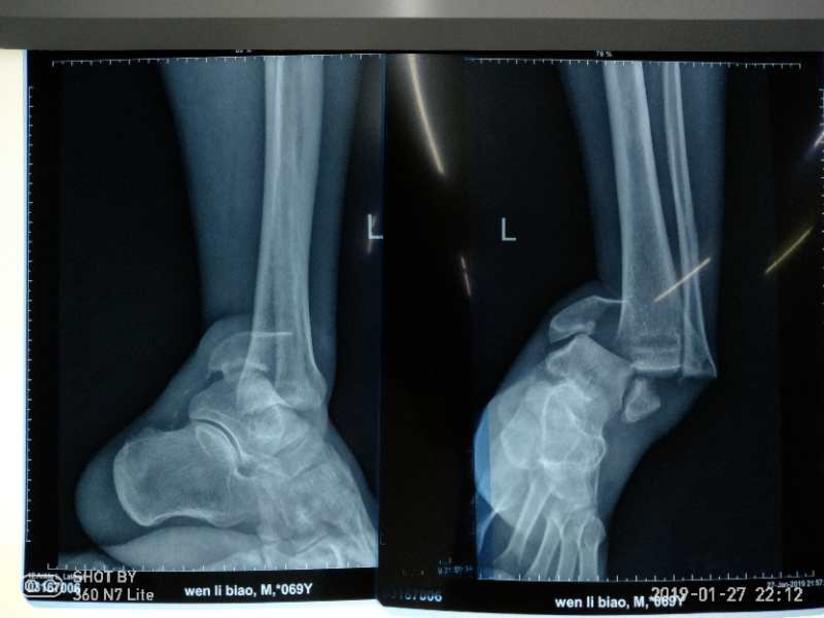

踝关节骨折 健康号 微医

足首脱臼骨折入院5 7目 足関節観血的手術 激痛 リハビリ開始 ひにログ